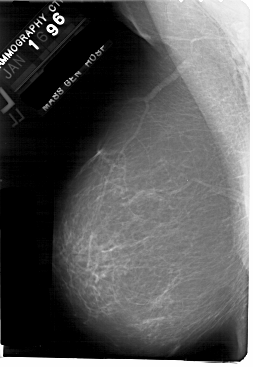

A_1869_1.RIGHT_MLO

RIGHT_MLO LINES 5491 PIXELS_PER_LINE 3781 BITS_PER_PIXEL 12 RESOLUTION 43.5 NON_OVERLAY